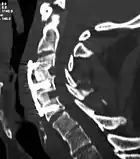

![]() X-rays of anterior cervical discectomy and fusion, C5C6 and C6C7. Lateral view. | |